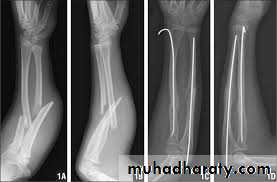

B-ADULTS

Unless the fragments are in close apposition, reduction is difficult and re-displacement in the cast almost invariable. So open reduction and internal fixation from the outset.

The fragments are held by interfragmentary

compression with plates and screws. Bone grafting is advisable if there is comminution.

It takes 8–12 weeks for the bones to unite.